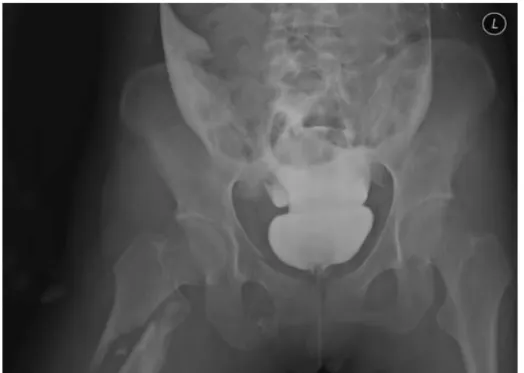

(1) Gold standard : Retrograde cystogram

•

At least 350cc, retrograde fashion through indwelling bladder catheter

조영제의 누출과 방광 손상부위

◦

복강 내로 누출 : intraperitoneal rupture 의미.

방광근처 후복막으로 누출 : extraperitoneal rupture 의미.

Bladder rupture